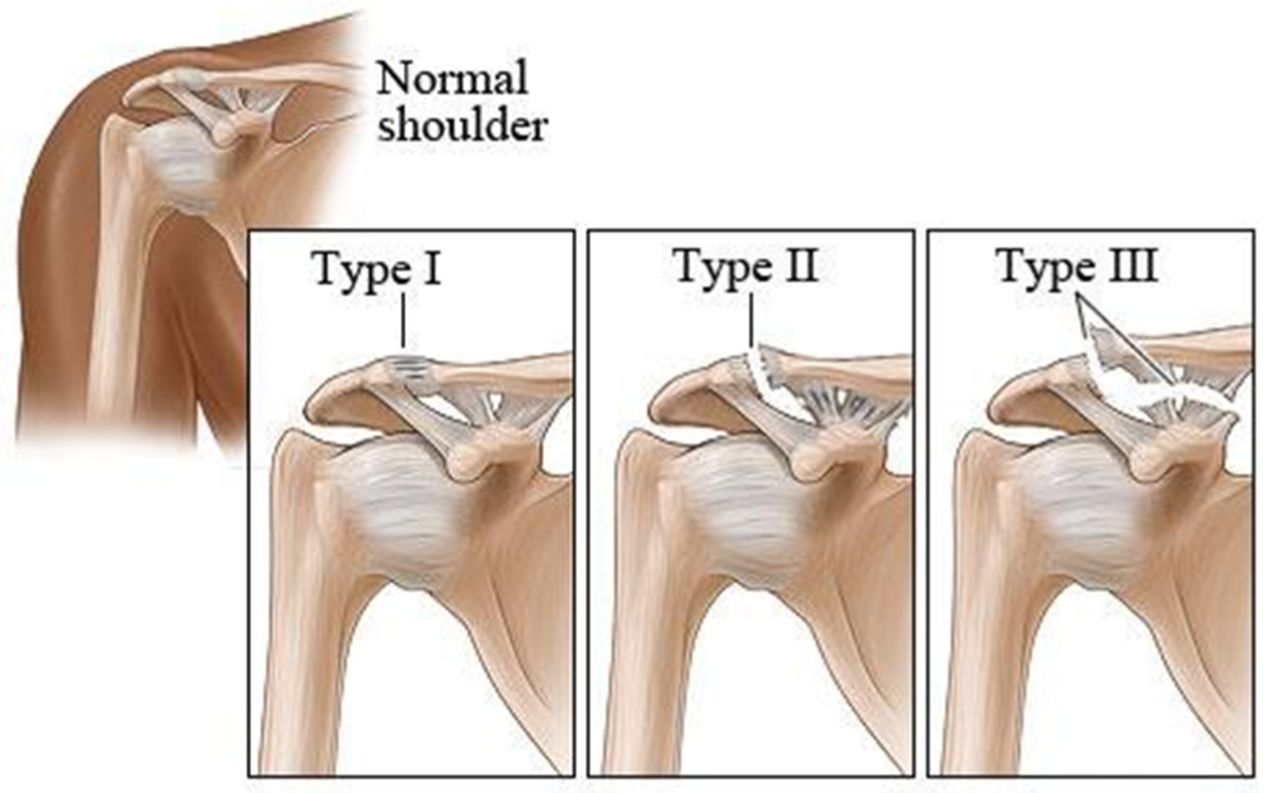

Diagnose this injury. Provide Moi, signs and symptomsand management

acromioclavicular joint sprain

moi - fall on outstreched arm/ tip of shoulder

signs and symptoms - grade 1 - mild pain, point tenderness, no visable deformity, mild stretching on coracoclavicular and aromioclavicular ligaments, grade 2 - moderat pain, pint tenderness, swelling, rupture of acromioclavicular ligament, unable to abduct/adduct shoulder through full rom , grade. 3- severe pain, point tenderness, rupture of acromioclavicular and coracoclavicular ligamanets, complete disclocation managament - POLICE, immobilisation in sling for 6 weeks, mobilization, flexibility and strengthening